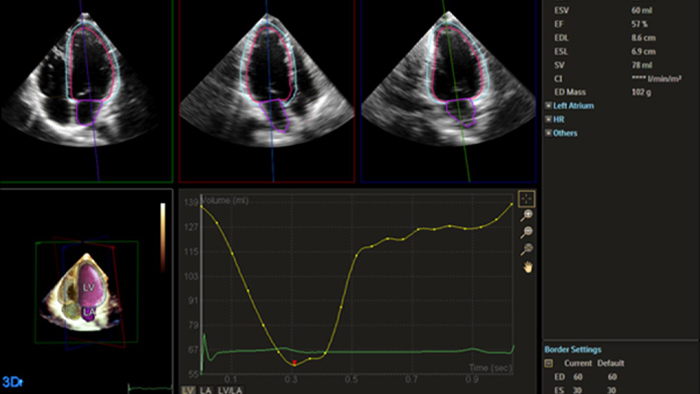

Robust and reproducible imaging tools are important to diagnose and monitor disease progression in heart failure. Current guidelines support the use of advanced echocardiography tools such as longitudinal strain and 3D assessment of LV and RV volumes and function.

Automation for robust, proven reproducible cardiac quantification in both 2D and 3D.

Quantification through Dynamic HeartModel.